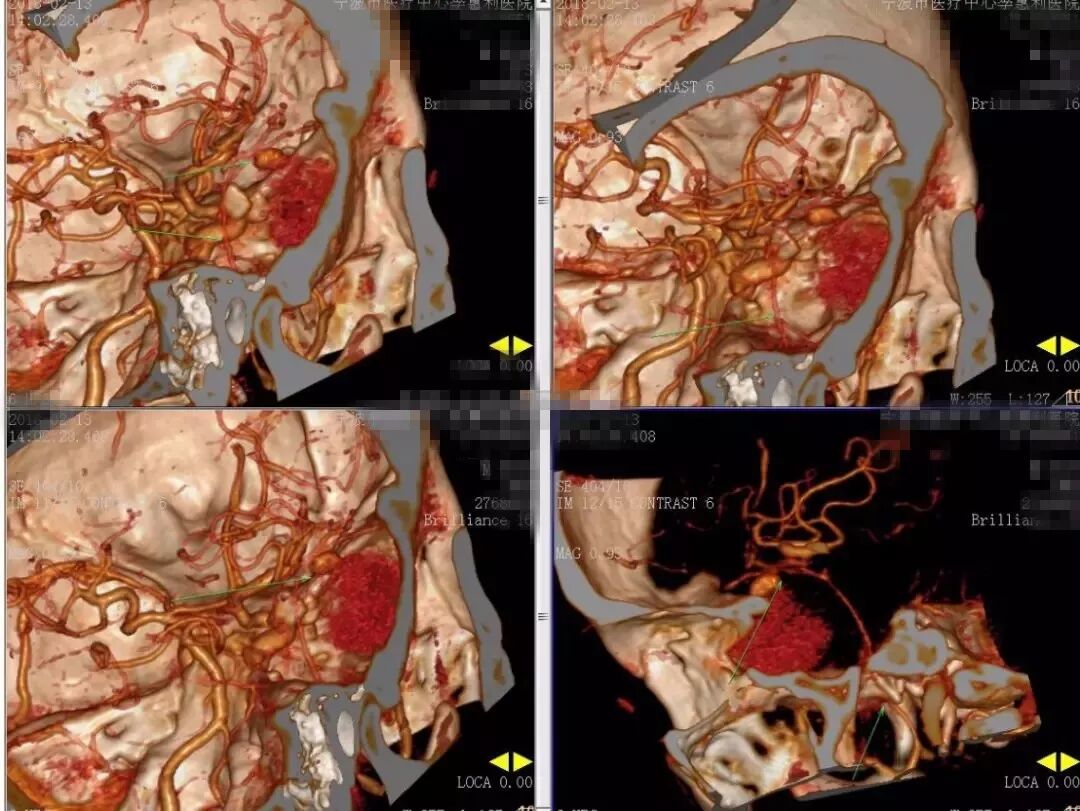

2018-2-13 CTA提示右颞部DAVF可能(图6),建议DSA。仔细阅片CTA未见明显引流静脉,考虑右侧脑膜中动脉假性动脉瘤可能更大。次日行 DSA检查,证实为“右侧脑膜中动脉假性动脉瘤”(图7)。当日即行“右侧翼点入路,脑膜中动脉假性动脉瘤切除加血肿清除术”(图8)。病理回报:镜下纤维细胞增生,可见血凝块伴机化(图9)。2018-2-27 复查CTA提示右侧脑膜中动脉假性动脉瘤术后改变,未见残余及复发(图10)。

图6. 2018-2-13 CTA提示右颞部DAVF可能。

图10. 2018-2-27 复查CTA提示右侧脑膜中动脉假性动脉瘤术后改变,未见残余及复发。